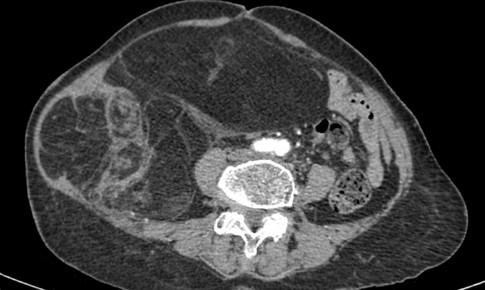

SKĐS - Chiều 3/11, thông tin từ Bệnh viện Ung Bướu Hà Nội cho biết các bác sĩ Khoa Ngoại Tổng hợp của bệnh viện vừa thực hiện thành công phẫu thuật cắt bỏ một khối u ác tính mô mềm hiếm gặp kích thước 28 × 15 cm, nặng gần 4 kg, ở bệnh nhân nữ 76 tuổi...